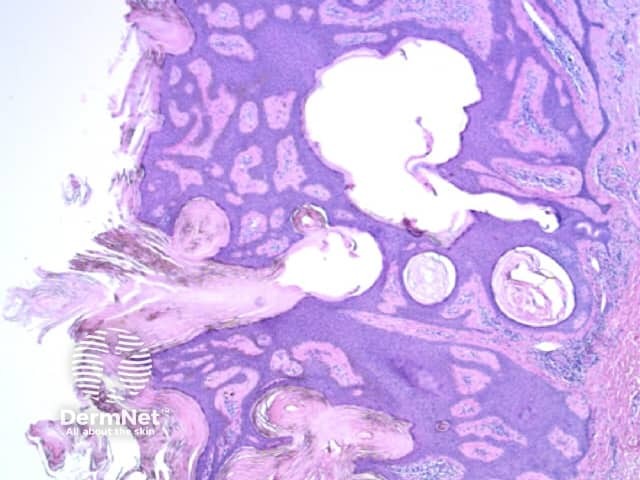

Seborrhoeic keratoses are amongst the most variable lesions on dermatoscopy, which is reflected in their protean histological appearances (Figure 15). Aside from the pseudopod pattern, any pattern or colour can be found. Flat seborrhoeic keratoses appear similar to solar lentigo on dermatoscopy. With early epidermal acanthosis thin curved lines (Figure 13) and circles become manifest, whilst with advanced acanthosis thick curved lines (Figure 14) and clods typically predominate. White clods are due to keratin under the stratum corneum. Orthokeratotic loosely laminated surface keratin appears yellow. Crypts fill with discoloured keratin and may appear various colours on dermatoscopy including brown and orange (Figure 15).

Figure 12